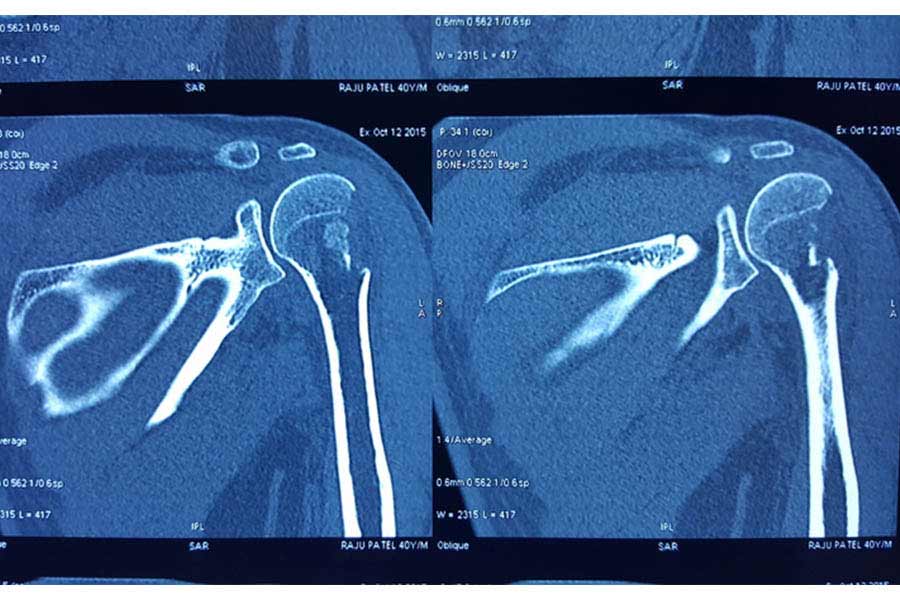

Trauma

Case 1